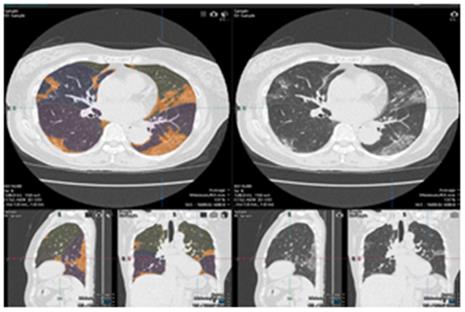

(2) 新冠肺炎图像测定功能可以清晰显示肺部感染区域。

图:新冠肺炎解析软件示例图(摘自日本藤田医科大学官网)